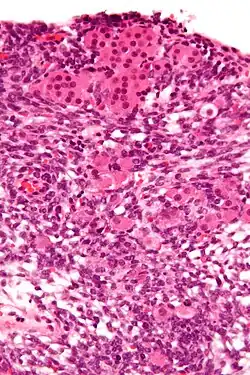

Das Androblastom [Etymologie: griechisch ἀνδρὀς = Mann und Blastom] (Syn. Arrhenoblastom; griechisch ἅρρην = Mann) ist ein sehr seltener Tumor der Keimdrüsen, der sowohl bei Männern im Hoden als auch bei Frauen im Eierstock auftreten kann. Es handelt sich um Tumoren, die von den Sertoli-Zellen, den Leydig-Zwischenzellen oder von beiden ausgehen können. Sie können hoch- oder mittelgradig differenziert, aber auch sarkomartig entdifferenziert vorkommen. Häufig treten auch bis zu 20 % Komponenten anderer (heterologer) Gewebe (Knorpel, Skelettmuskulatur, mukoide Magen-Darm-Epithelien) auf.[1] Bei hohem Leydig-Anteil zeigt sich aufgrund der Testosteronbildung bei Frauen eine Virilisierung mit androgenem Zellbild in der Vaginalzytologie.[2]